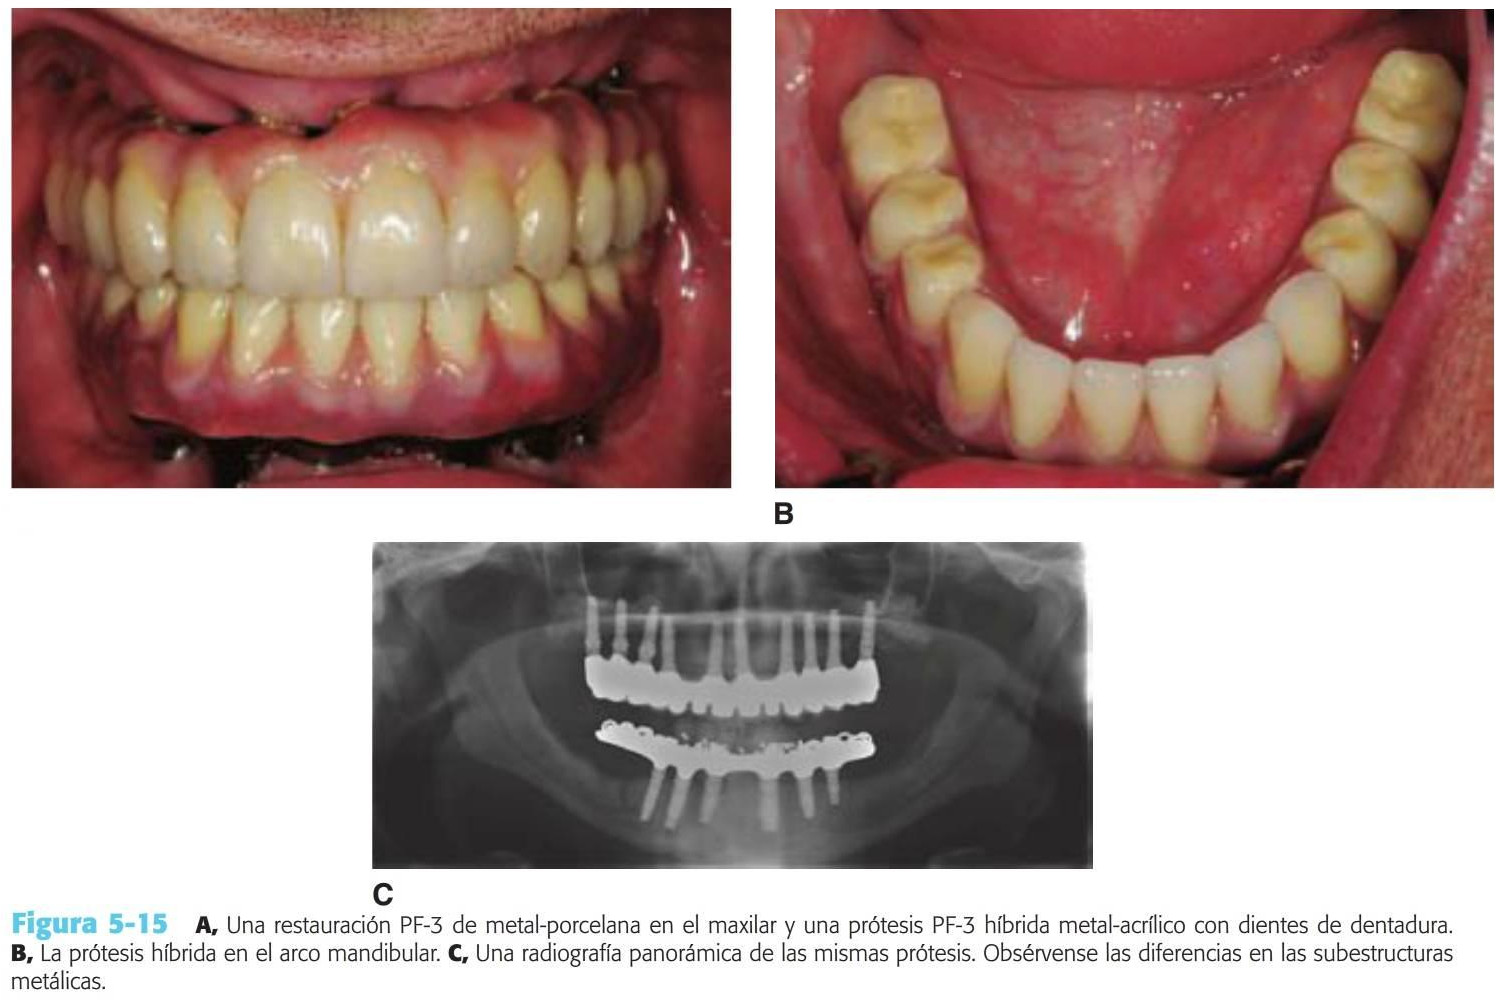

Básicamente existen dos enfoques para una prótesis PF-3: 1) una restauración híbrida compuesta por una dentadura con dientes con una subestructura acrílica y metálica o 2) una restauración de metal-porcelana (figs. 5-12 a 5-14; tabla 5-2).

Una alternativa a la prótesis tradicional fija de metal porcelana es la restauración híbrida (v. tabla 5-2). Este di seño utiliza una estructura metálica menor, con dientes artificiales y acrílico para unir estos elementos (fig. 5-15).

Esta restauración es menos cara de fabricar y es muy estética debido a los dientes artificiales prefabricados y al reemplazo de los tejidos blandos por el acrílico rosa. Además, el acrílico interpuesto entre los dientes y el armazón puede reducir fuerza de impacto de las cargas odusales dinámicas. La prótesis híbrida es más fácil de reparar ante una fractura, y el diente artificial puede sustituirse con un riesgo menor que el añadido de porcelana a una restauración tradicional ceramometálica. En cualquier caso, la fatiga del acrílico es mayor que en las prótesis tradicionales; de ahí que la reparación de la restauración se necesite con más frecuencia.

La determinación del espacio vertical de la corona de una restauración híbrida frente a una restauración tradicional de metal-porcelana es de 15 mm desde el hueso hasta el plano oclusal. Cuando la dimensión de la que se dispone es inferior a esta, se sugiere emplear una restauración de metal-porcelana. Cuando existe un espacio vertical de la corona mayor, se suele fabricar una restauración híbrida.